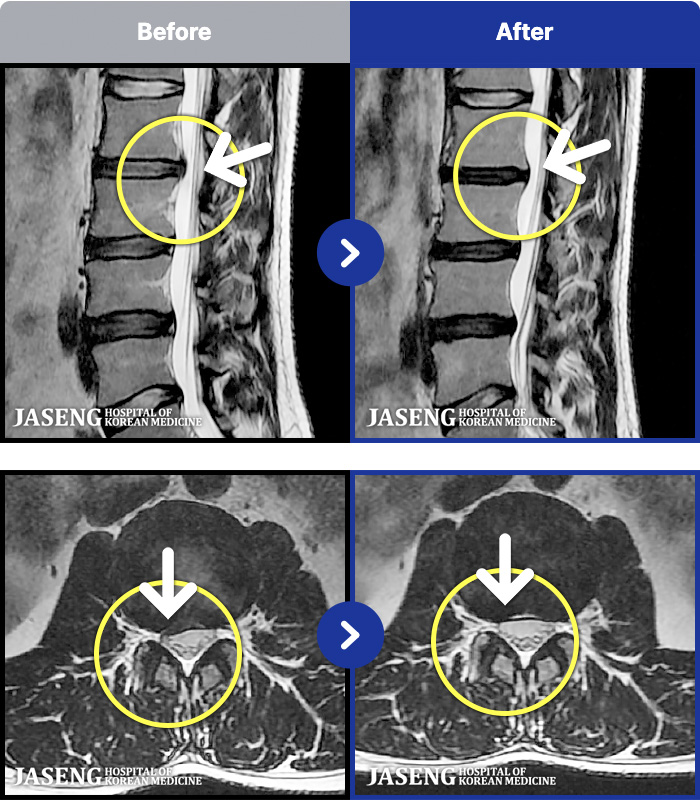

54 MRI ũ ʸ Ȯϼ.

ȯںп Ǹ ǿ ԿǾ, ο ġ ۿ Ƿ ġḦ Ͻñ ٶϴ.